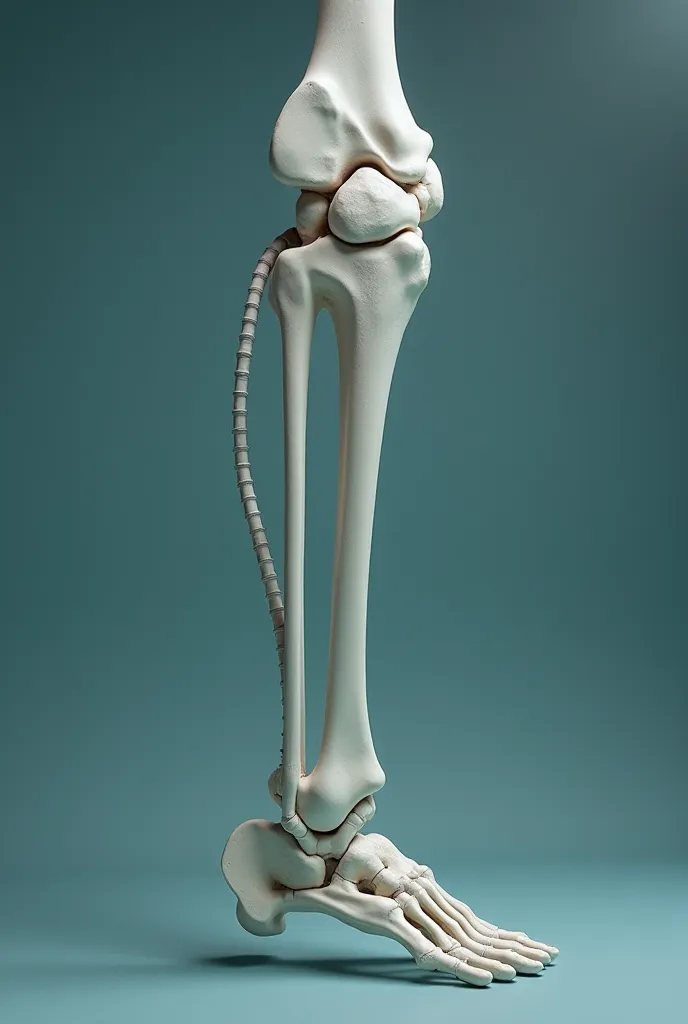

A close up of a white object with a human leg

Close-up of human knee,There is a bone in the middle, knee, Knees, surreal bone structure, Protruding bones, Realphotos, orthographic view, Look across the shoulder, medical depiction, Osteoarticular joints, computer generated, hyper realisitc, sharp bone structure, joint, digital painted

There is a bone in the middle

Protruding bones

orthographic view

medical depiction

Osteoarticular joints

sharp bone structure